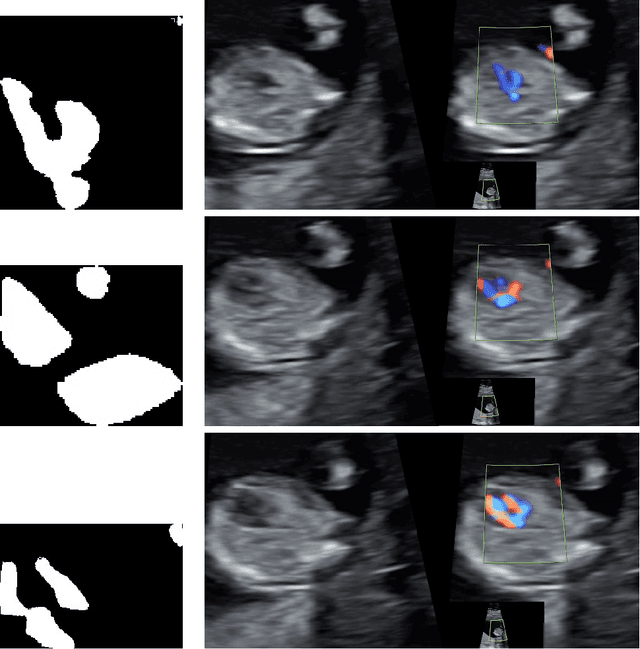

Abstract:The present paper puts forward an incipient study that uses a traditional segmentation method based on Zernike moments for extracting significant features from frames of fetal echocardiograms from first trimester color Doppler examinations. A distance based approach is then used on the obtained indicators to classify frames of three given categories that should be present in a normal heart condition. The computational tool shows promise in supporting the obstetrician in a rapid recognition of heart views during screening.